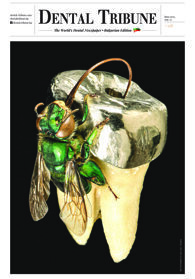

Плоскоклетъчният карцином в лицево-челюстната област е един от най-смъртоносните...

Злокачествените тумори на устната кухина са шестата водеща причина за смърт поради ...